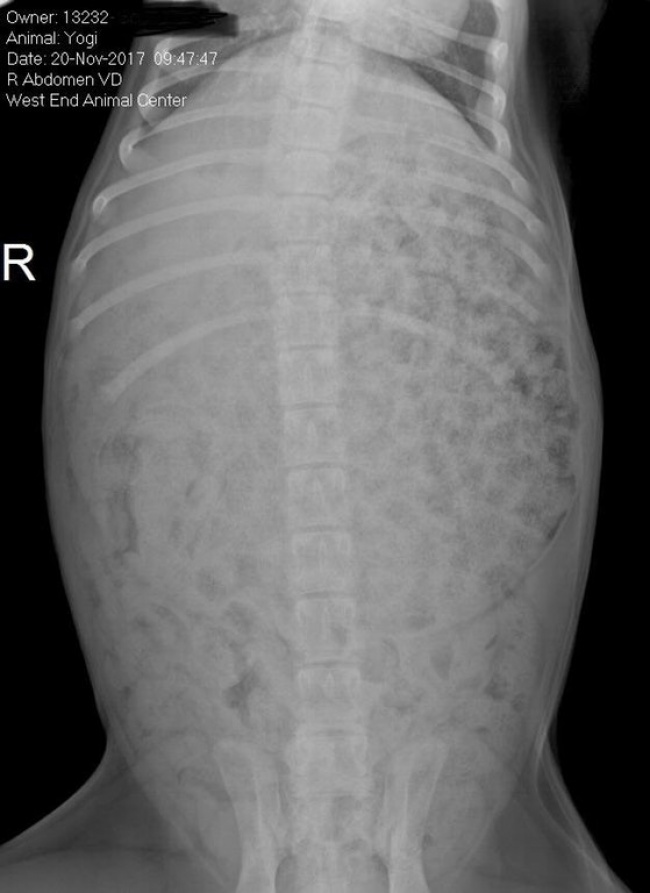

«Наш щеня лабрадора заліз у мішок з кормом минулої ночі. $ 250 потому я отримав цей рентгенівський знімок: жодного органу, суцільний шлунок»